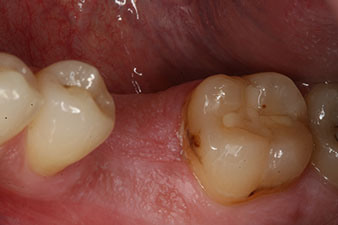

Fig. 1: Initial clinical situation after healing of extraction alveolus 36: The bone base is wide and there is sufficient keratinized gingiva.

A 28-year-old patient with a history of heavy smoking had to have tooth 36 extracted as a result of recurring apical periodontitis.

Due to the generally intact neighbouring teeth the only way to fill the gap was an implant.